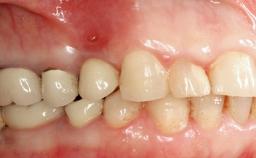

A 30-year-old female patient was referred to the Department of Periodontology of the University of Bern, Switzerland, by a dentist in private practice. Tooth 45 had been congenitally missing and had been replaced with a titanium implant three years prior to the first visit at the Department of Periodontology. The tissue level implant had a diameter of 4.1 mm, a length of 12 mm, and a sandblasted and acid-etched (SLA) surface (Straumann® Dental Implant System; Institut Straumann AG, Basel, Switzerland). The metal-ceramic crown on implant 45 had been cemented permanently. Implant 45 had been diagnosed with peri-implantitis by the referring dentist in the course of regular supportive care.